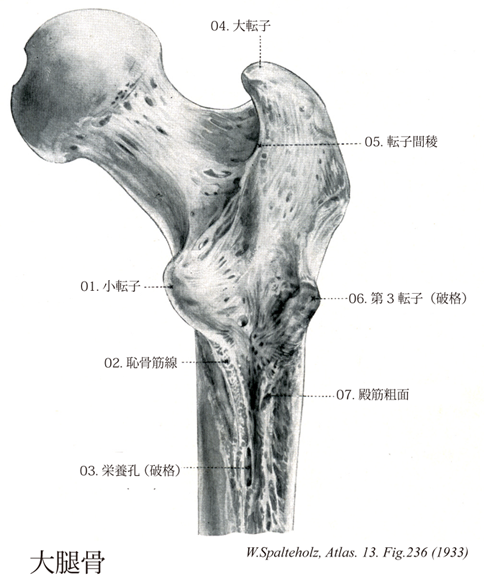

Spalteholz HANDATLAS DER ANATOMIE DES MENSCHEN VON WERNER SPALTEHOLZ

236

- 236_00【Femur; Thigh bone大腿骨 Femur; Os femoris】

→(大腿骨は人体で最長の管状骨で約40cmあり、身長のほぼ4分の1を占め、前方に軽く凸弯している。起立時遠位端は水平面上にあるが、大腿骨は垂直位をなさず、近位部が骨盤の幅だけ外方へずれる。また大腿骨頚の長軸と大腿骨遠位端の横軸とは同一平面上にはなく、大腿骨は長軸のまわりに骨頭が前方へ向く方向方向に約15度ねじれている。近位端(上端)で上内側やや前方へ突出する球状部が大腿骨頭であり、大腿骨頭の中心のやや後下方にある卵円形の粗面状小陥凹部分が大腿骨頭窩である。大腿骨頭と円柱状の大腿骨体を連結する細い部分が大腿骨頚で、大腿骨頚の中央部は細いが内および外側端で、とくに外側端で幅が広く前後にやや扁平となる。上縁は水平に、下縁は外下後方へ斜めに走っている。大腿骨頚と大腿骨体は、約125度の傾斜度で連結している。角度は生下時により成熟するにしたがい小さくなる。男性より女性の方が角度が小さい。大腿骨頚と大腿骨体との結合部の上外側にある大きな隆起が大転子で、結合部の後下部から内後方へ突出する部分が小転子である。大転子の後上部は上内側へ突出しやや深い陥凹部をつくる。この陥凹部が転子窩である。大転子の前面上内側部から大腿骨頚の前面を下内方に走り頚の下縁で小転子の前面にいたる粗な隆線が転子間線で、大腿骨頚と大腿骨体との結合部に相当する。転子間線は内下方へ伸びて渦状線へつづき、また下端近くで結節状に隆起して2次結節となることがある。大転子の後上角部から後面を下内包へ走り小転子にいたる比較的縁が丸い隆起が転子間稜で、頚と体との結合部に相当する。転子間稜の中央やや上外側部にある低い膨隆部分が方形筋結節である。円柱状の大腿骨体は中央部で細い上部で太く、下部では左右に幅が広くなる。大腿骨の長軸は立位で約10度脛骨の垂直線に対して外側へ傾いている。大腿骨体の中央1/3では3縁・3面がある。内側縁と外側縁は丸味をおびている。各3面とも平滑で、前面は内側縁と外側縁との間にあって前方へ凸面をなす。外側面は外側縁と後縁との間にあり、外側よりむしろ後方に面している。内側面は内側縁と後縁との間にあり内方やや後方にむいている。後縁の粗で幅広い線状隆起が粗線である。粗線の内および外側で稜状に隆起した部分がそれぞれ内側唇と外側唇で、栄養孔がこの両者の間で認められる。大腿骨体の上1/3では粗線が3本の線状隆起として拡散し、逆三角形の粗線である後面を形成する。下方で内側唇に、上方で転子間線の下端につづく内側の細い線状隆起が渦状線である。内側唇から小転子の基部へいたる中間位の線状隆起が恥骨筋線で、外側唇から上外方大転子の基部へ走る幅がある粗な線状隆起が臀筋粗面である。臀筋粗面は近位部で隆起し第三転子をつくることがある。大腿骨体の下1/3では内側部が前後に扁平化し、下端が広い三角柱状を呈する。内側唇は内下方の内側顆の後上方に、外側唇は外下方外側顆の後上方にいたる。前者が内側上顆線、後者が外側上顆線である。これらに境され浅く陥凹した三角形の平滑な面が膝蓋面である。内側上顆線の上方は大腿動脈が斜走するため不明瞭となっている。大腿骨の遠位端(下端)大きく膨隆している。内側の隆起が内側顆、外側の隆起が外側顆である。内側窩は内下方および後方へ、外側顆は下方・後方および前上方に突出する部分が内側上顆で、内側上顆上方の小さな突起が内転筋結節である。外側顆は内側顆より外側への膨隆度が小さく、大腿骨体の外側面からほとんどでていない。外側面後上方で外側へ突出する部分が外側上顆である。内側顆と外側顆は大腿骨の前面で互いに連絡するが、後面では深い間隙で隔てられている。この間隙が顆間窩である。内側顆と外側顆の後縁を結ぶ稜状隆起が顆間窩で、顆間窩の上縁をなし膝蓋面との境をなす。前下方は膝蓋面の下縁で境される。内側顆と外側顆の下面および後面の凸面をなす帯状の関節面が脛骨上端と関節する脛骨面である。脛骨面は内側顆にあり前外方へ弯曲する内側部と、外側顆にあり幅広く前後に直線的に走る外側部とに分けられる。内外の両側部が両顆の前方で互いに癒合し、膝蓋骨後面に接する関節面が膝蓋面である。膝蓋面は中央の縦溝で内外に二分されるが、外側部が大きい。ラテン語のFemur(大腿)に由来する。)

- 236_01【Lesser trochanter of femur小転子(大腿骨の) Trochanter minor】 Small prominence on the posterior aspect of the femur projecting medially from the junction of the neck and shaft. Attachment site of the iliopsoas muscle.

→(大腿骨頚の下内側後方には小転子が突出している。腸腰筋が着く。)

- 236_02【Pectineal line of femur; Spiral line恥骨筋線(大腿骨の) Linea pectinea pectinea femoris】 Bony line extending inferiorly from the lesser trochanter, nearly reaching the linea aspera. Attachment site of the pectineus muscle.

→(小転子の後面から、小転子の縁の下方へのつづきに合する縦走する粗な線が走る。これは恥骨筋の着く恥骨筋線である。)

- 236_03【Nutrient foramen栄養孔 Foramen nutricium】 Opening of the nutrient canal at the surface of the bone.

→(どの骨をとってみても、骨の表面には虫が食ったような孔がポツポツとあいている。これらのうち、こまかい孔やくぼみは主としてシャーピーの線維(骨膜から骨質に入り込む結合組織線維)が侵入する孔であるが、輪郭のハッキリした直径1~2mmの丸い穴は細い血管が骨に出入りするためのもので、栄養孔とよばれる。厳密にいえば、これらの孔の開口部が栄養孔で、骨に入り込んだトンネル状の部分は栄養管と名づけられる。この栄養孔ないし栄養管は骨質を貫いて髄腔(骨髄を収容する腔所)に達している。したがって、栄養孔からはいる動脈は主として骨髄を養うが、その枝は髄腔に近い深部の骨質も養う。また栄養孔から出てくる静脈は骨髄と骨からの炭酸ガスや老廃物を運ぶだけでなく、骨髄で形成された新しい赤血球や白血球を末梢血流に導き出す役割を持っているのである。なお骨の表層の緻密質は、骨膜の動脈叢から出る無数の細い枝で養われが、その進入路は非常に細くて肉眼的にはほとんど見分けられない。それぞれの骨における栄養孔の数や位置は、大体の原則はあるものの個体差ははなはだしい。たとえば椎骨では、栄養孔はとくに椎体の表面に多くみられるが、その数・位置・大きさなどは千差万別でる。なお、椎孔をのぞきこんでみると、椎体の後面にはとくに大きい栄養孔(ここを通る主な血管は椎体静脈)を見いだすことができる。)

- 236_04【Greater trochanter of femur大転子(大腿骨の) Trochanter major】 Large prominence on the superolateral aspect of the femur for attachment of the gluteus medius, gluteus minimus, and piriformis muscles.

→(大腿骨頚の上外側には大転子(中臀筋、小臀筋、梨状筋がつく)が突出している。転子とはハンドルのことで、その力学的な効用は、たとえば大転子につく中臀筋が大腿骨を外転させている。)

- 236_05【Intertrochanteric crest転子間稜 Crista intertrochanterica】 Bony ridge extending on the posterior aspect of the femur from the greater to the lesser trochanter.

→(大転子と小転子を結ぶ稜線は転子間稜と呼ばれる。大腿方形筋がつく。)

- 236_06【Third trochanter第3転子 Trochanter tertius】 Projection occasionally found at the base of the greater trochanter at the end of the linea aspera. Attachment site for a portion of the gluteus maximus muscle.

→(臀筋粗面が著しく高くなって第三転子をつくることがある。日本人では30%近くに見られるというが、どのくらい発達すれば第三転子と呼ぶのか基準の定めかた次第でこの頻度は変わってくる。)

- 236_07【Gluteal tuberosity殿筋粗面;臀筋粗面 Tuberositas glutea】 Roughened, elongated area prolonging the lateral lip to superior. It affords insertion to the gluteus maximus muscle.

→(外側唇は上方は大転子の下方に達し、細長い臀筋粗面をつくる。臀筋粗面が著しく高くなって第三転子をつくることがある。)